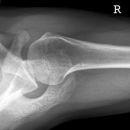

Schulter seitlich (Y-View)

Bei Luxation zusätzlich zur glenoidtangentialen Aufnahme problemlos durchführbar! Axiale Aufnahme schmerzbedingt meist nicht möglich.

Beurteilungskriterien

- Skapula bildet sich als Y ab

- Humeruskopf projiziert sich in das Glenoid? Luxation? Luxationsrichtung?

- Weite des subacromialen Raumes exakt nur in der 10 – 15° nach kaudal angulierten Aufnahme bestimmbar („Morrison, Outlet View“)! Normalerweise 1 - 1,5 cm, < 6 mm -> wohl pathologisch, Impingment wahrscheinlich

- Normvarianten: Os glenoidale (akzessorischer Ossikel kaudal des Glenoids), persistierende Akromion- oder Korakoidapophyse, entwicklungsbedingte Pfannenranddefekte

- Schulterluxationen:

- Anteriore Luxation (2) 95%= anteriore infraglenoidale Luxation, Kopf liegt vor Glenoid

- Posteriore Luxation (2) 3%: wird häufig übersehen! Kopf liegt hinter Glenoid, Hochstand des Humeruskopfes, fixierte Innenrotation des Humeruskopfes => atypische Projektion des Humeruskopfes: “ drumstick or bulb appearance“ (Birnenform), Muldenzeichen („trough line“), „rim sign“ in der ap bzw. glenoidtagentialen Aufnahme.

Zweite Ebene, z.B. transskapuläre Aufnahme zeigt die Richtung der Luxation. Cave. rein klinische Diagnose!

- Begleitverletzungen? (-> heute umfassend mit CT/MRT zu beurteilen)

- Tuberculum majus (15%)

- Pfannenrand

- Hill- Sachs Läsion = Dorsokraniale Humeruskopf-Impressionsfraktur (50%) (Aufnahme der 1. Wahl: Stryker oder CT)

- umgekehrte Hill-Sachs Läsion = anteromediale Impression nach hinterer Luxation

- Bankart-Läsion: Abriss des vorderen Labrum-Kapsel-Komplexes bzw. Abrissfraktur des vorderen unteren Glenoidrandes (-> CT-Athrographie, Arthro-MRT)